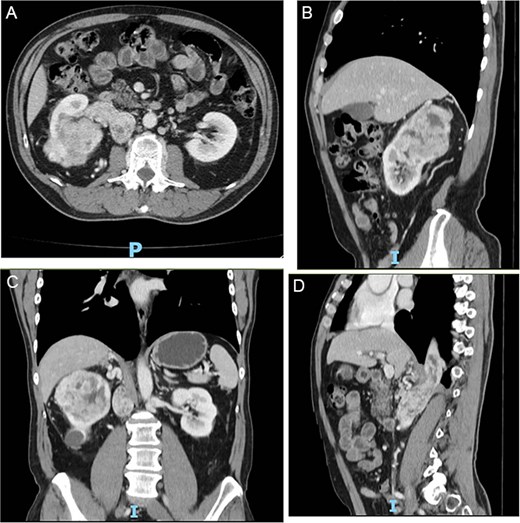

The authors present the case of a 60-year-old male patient with a recent diagnosis of T2a melanoma on the back, with no indication for adjuvant therapy, who underwent an abdominopelvic computed tomography with an incidental finding of a hypervascular solid mass in the right lower renal pole, compatible with an organic lesion measuring 8.5 × 7 × 8 cm invading the renal vein and the azygos vein, with intrathoracic extension (Fig 2A–D). The patient presents a vascular anomaly characterized by agenesis of the retrohepatic portion of the IVC. The hepatic veins drain directly into the right atrium, while the azygos vein serves as an alternative venous pathway, draining into the superior vena cava. A thrombus extends through the azygos vein into its intrathoracic portion.

(A–D) Abdominopelvic contrast-enhanced computed tomography prior to neoadjuvant therapy showing a lesion in the right kidney with associated mural thrombus extends through the azygos vein in the sagittal section.